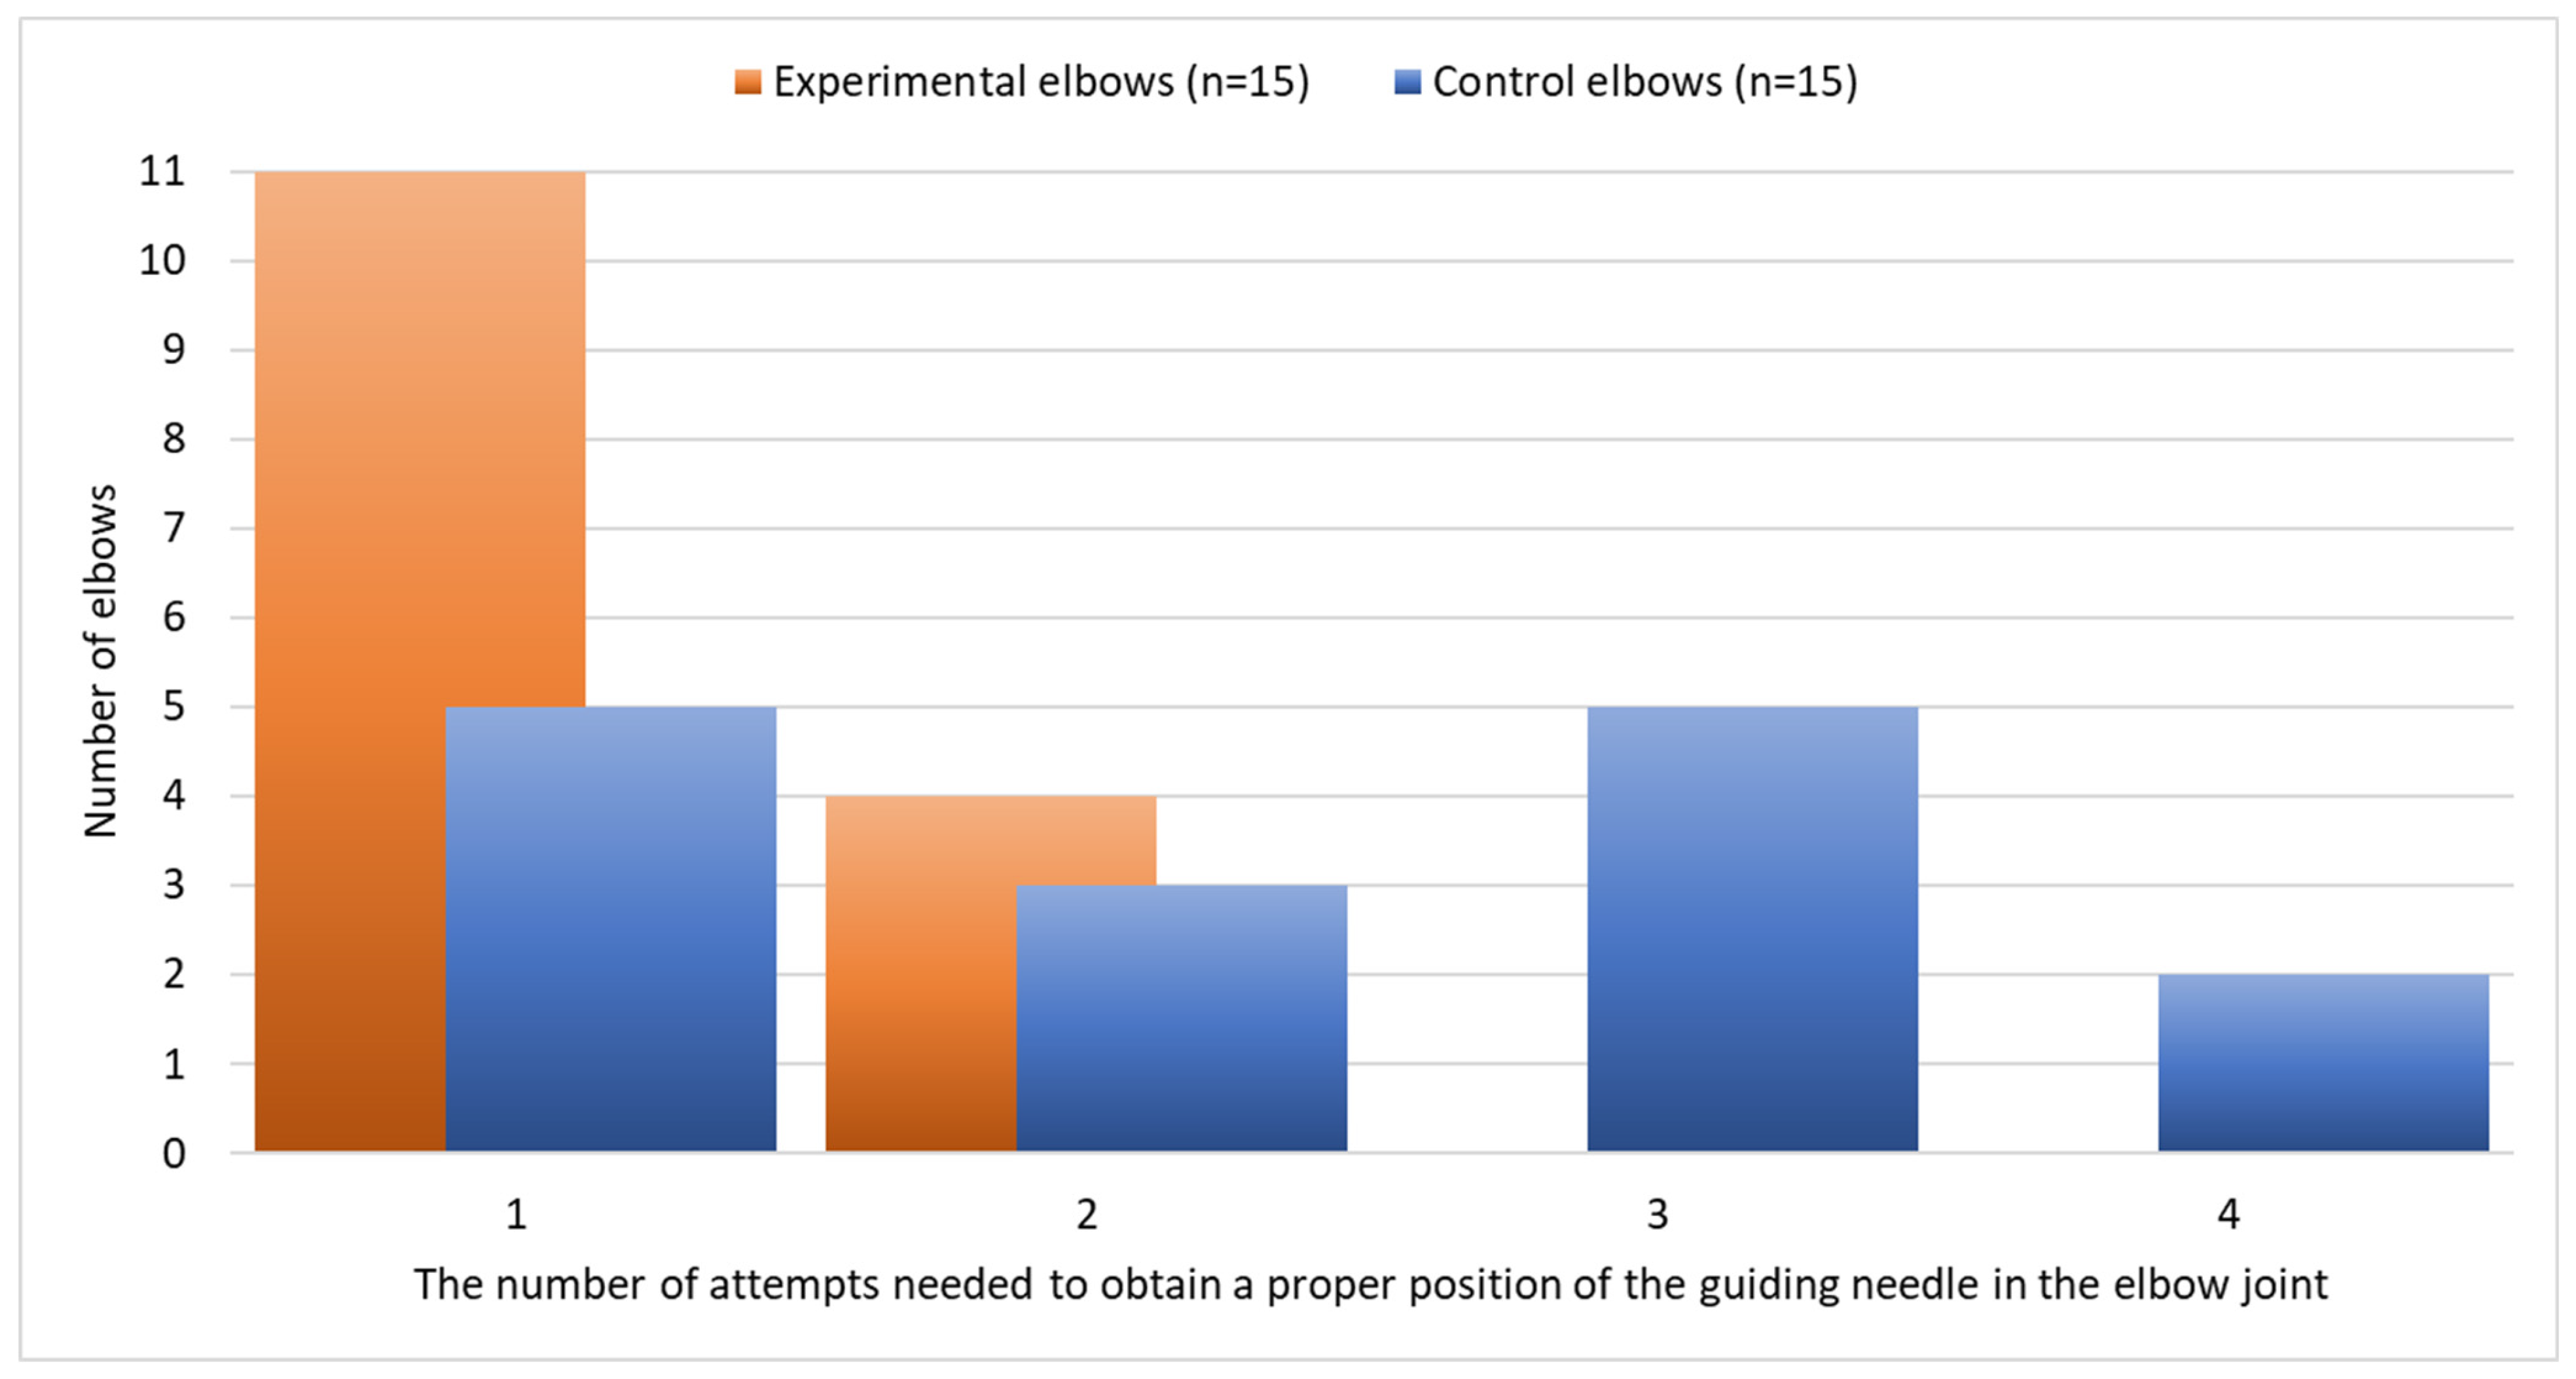

3. Results

3.2. Cadaver Studies

| No. | Cadaver Characteristics | Elbow | Number of Attempts Needed to Place the Guiding Needle Properly | |||||

|---|---|---|---|---|---|---|---|---|

| Breed | Sex | Age (Years) | Body Weight (kg) | Left | Right | Custom-Made Arthroscopic Aiming Device (Experimental Elbow) | Free Hand (Control Elbow) | |

| 1 | Crossbreed | male | 5 | 31 | 1 | 1 * | 1 | 1 |

| 2 | Boerboel | male | 6 | 57 | 1 * | 2 | 1 | 2 |

| 3 | Newfoundland | male | 2 | 45 | 1 * | 4 | 1 | 4 |

| 4 | Labrador retriever | male | 2 | 29 | 3 | 1 * | 1 | 3 |

| 5 | Crossbreed | male | 2 | 19 | 1 | 1 * | 1 | 1 |

| 6 | German Shepherd | male | 3 | 35 | 2 * | 1 | 2 | 1 |

| 7 | Chow-chow | female | 1 | 17 | 1 * | 3 | 1 | 3 |

| 8 | Crossbreed | female | 6 | 35 | 1 | 1 * | 1 | 1 |

| 9 | Golden retriever | female | 4 | 32 | 2 | 1 * | 1 | 2 |

| 10 | Crossbreed | male | 3 | 25 | 3 | 2 * | 2 | 3 |

| 11 | Labrador retriever | male | 6 | 35 | 2 * | 4 | 2 | 4 |

| 12 | Staffordshire Bull Terrier | male | 2 | 17 | 1 * | 1 | 1 | 1 |

| 13 | Crossbreed | female | 5 | 20 | 1 * | 2 | 1 | 2 |

| 14 | Labrador retriever | female | 4 | 30 | 2 * | 3 | 2 | 3 |

| 15 | Staffordshire Bull Terrier | female | 6 | 27 | 3 | 1 * | 1 | 3 |

| Descriptive statistics | ||||||||

| Median | 4 | 30 | 1 | 1 | 1 | 2 | ||

| Range | 1 | 17 | 1–3 | 1–4 | 1–2 | 1–4 | ||

| p-value | 6 | 57 | 0.625 | 0.009 | ||||